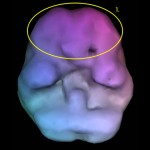

ADD je resničen, lahko ga vidimo v možganih. Na podlagi raziskav tisoče klientov z ADD motnjo sedaj vemo, na katerih možganskih predelih se kaj dogaja in tako smo dobili odgovore, zakaj takšen negativen vpliv na učenje, vedenje in čustvovanje.

Brain map pri tem tipu pokaže povišano počasno možgansko valovanje med koncentracijo v prefrontalnem predelu in bazalnih ganglijih. Ravno bazalni gangliji so strukture globoko v možganih, ki so zadolžene za produkcijo dopamina.